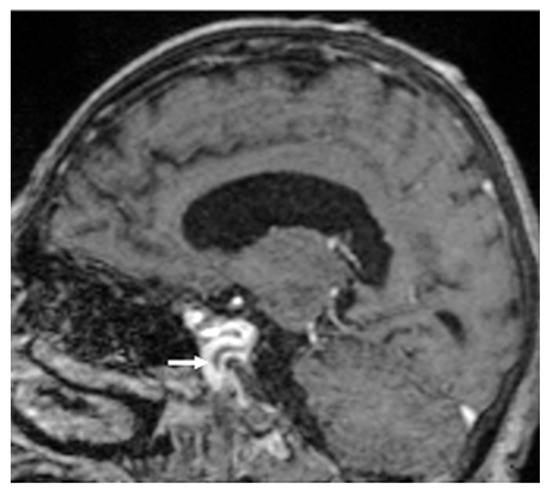

Fatal Complications in Candida parapsilosis Endocarditis—A Case Report

by

Sebastian George Smadu, Simona Camelia Tetradov, Luminita Ene, Simin Aysel Florescu and Dragos Stefan Lazar

J. Fungi 2025, 11(11), 817; https://doi.org/10.3390/jof11110817 (registering DOI) - 18 Nov 2025

Fungal endocarditis, despite being a rare diagnosis, has a higher morbidity and mortality rate compared to bacterial endocarditis. Candida species are the most common isolated pathogens involved in fungal endocarditis. Diagnosis is suspected in patients with underlying conditions such as cancer, myelodysplastic syndrome, diabetes, or intravascular catheters, where the modified Duke criteria apply. Management of the patient requires a multidisciplinary team (cardiologist, infectious diseases consultant, cardiac surgeon) along with antifungal treatment. We present the case of a 60-year-old male with biological prosthetic aortic valve replacement in the previous year for bicuspid aortic stenosis, admitted for a 5-day history of fever, nausea and minor urinary symptoms. The blood cultures were positive for Candida parapsilosis. Transthoracic cardiac ultrasound revealed a hypoechogenic mass attached to the aortic valve at the prosthetic fixation site. Although diagnosis was rapidly confirmed and treatment was administered shortly after first suspected, the patient developed, at first, cavernous sinus thrombosis and, later, fatal ST elevation myocardial infarction. The patient died despite efficient antifungal therapy, initially with Anidulafungin in monotherapy and later in combination with Fluconazole. The reported case emphasizes the importance of managing fungal endocarditis, the need for urgent diagnostic attention and multidisciplinary team approach by infectious diseases specialist, cardiologist, neurologist and heart surgeon.

Figure 1